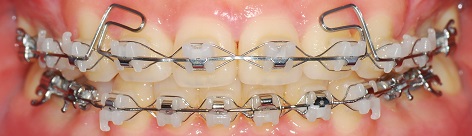

정면사진입니다

이제 위아래 중심도 맞겟다

저번달과 동일하게 고무줄을 끼고 지내는 것입니다.

치아를 좀 더 튼튼하게 유지하기 위해

좀 더 유지하고 장치를 제거하는 것으로 했습니다.